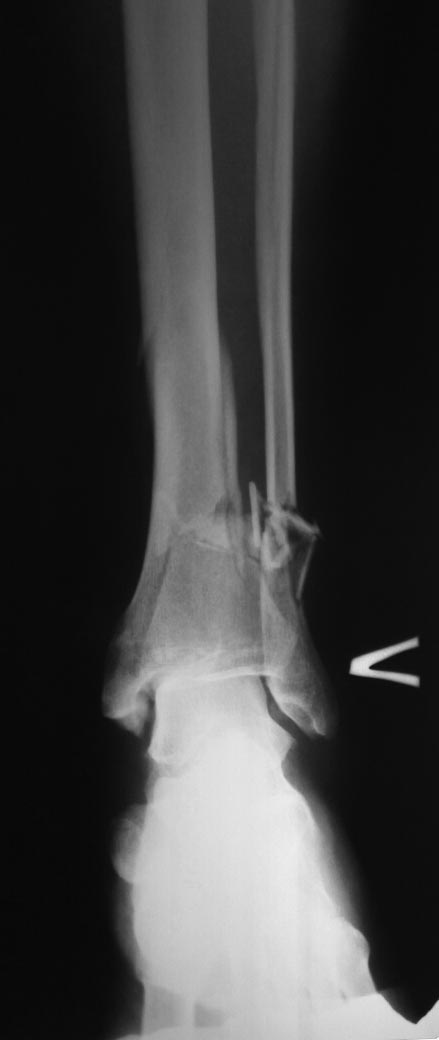

[Ortho] перелом типа "Пилон".

добавляю прямой. КТ к сожалению нет.